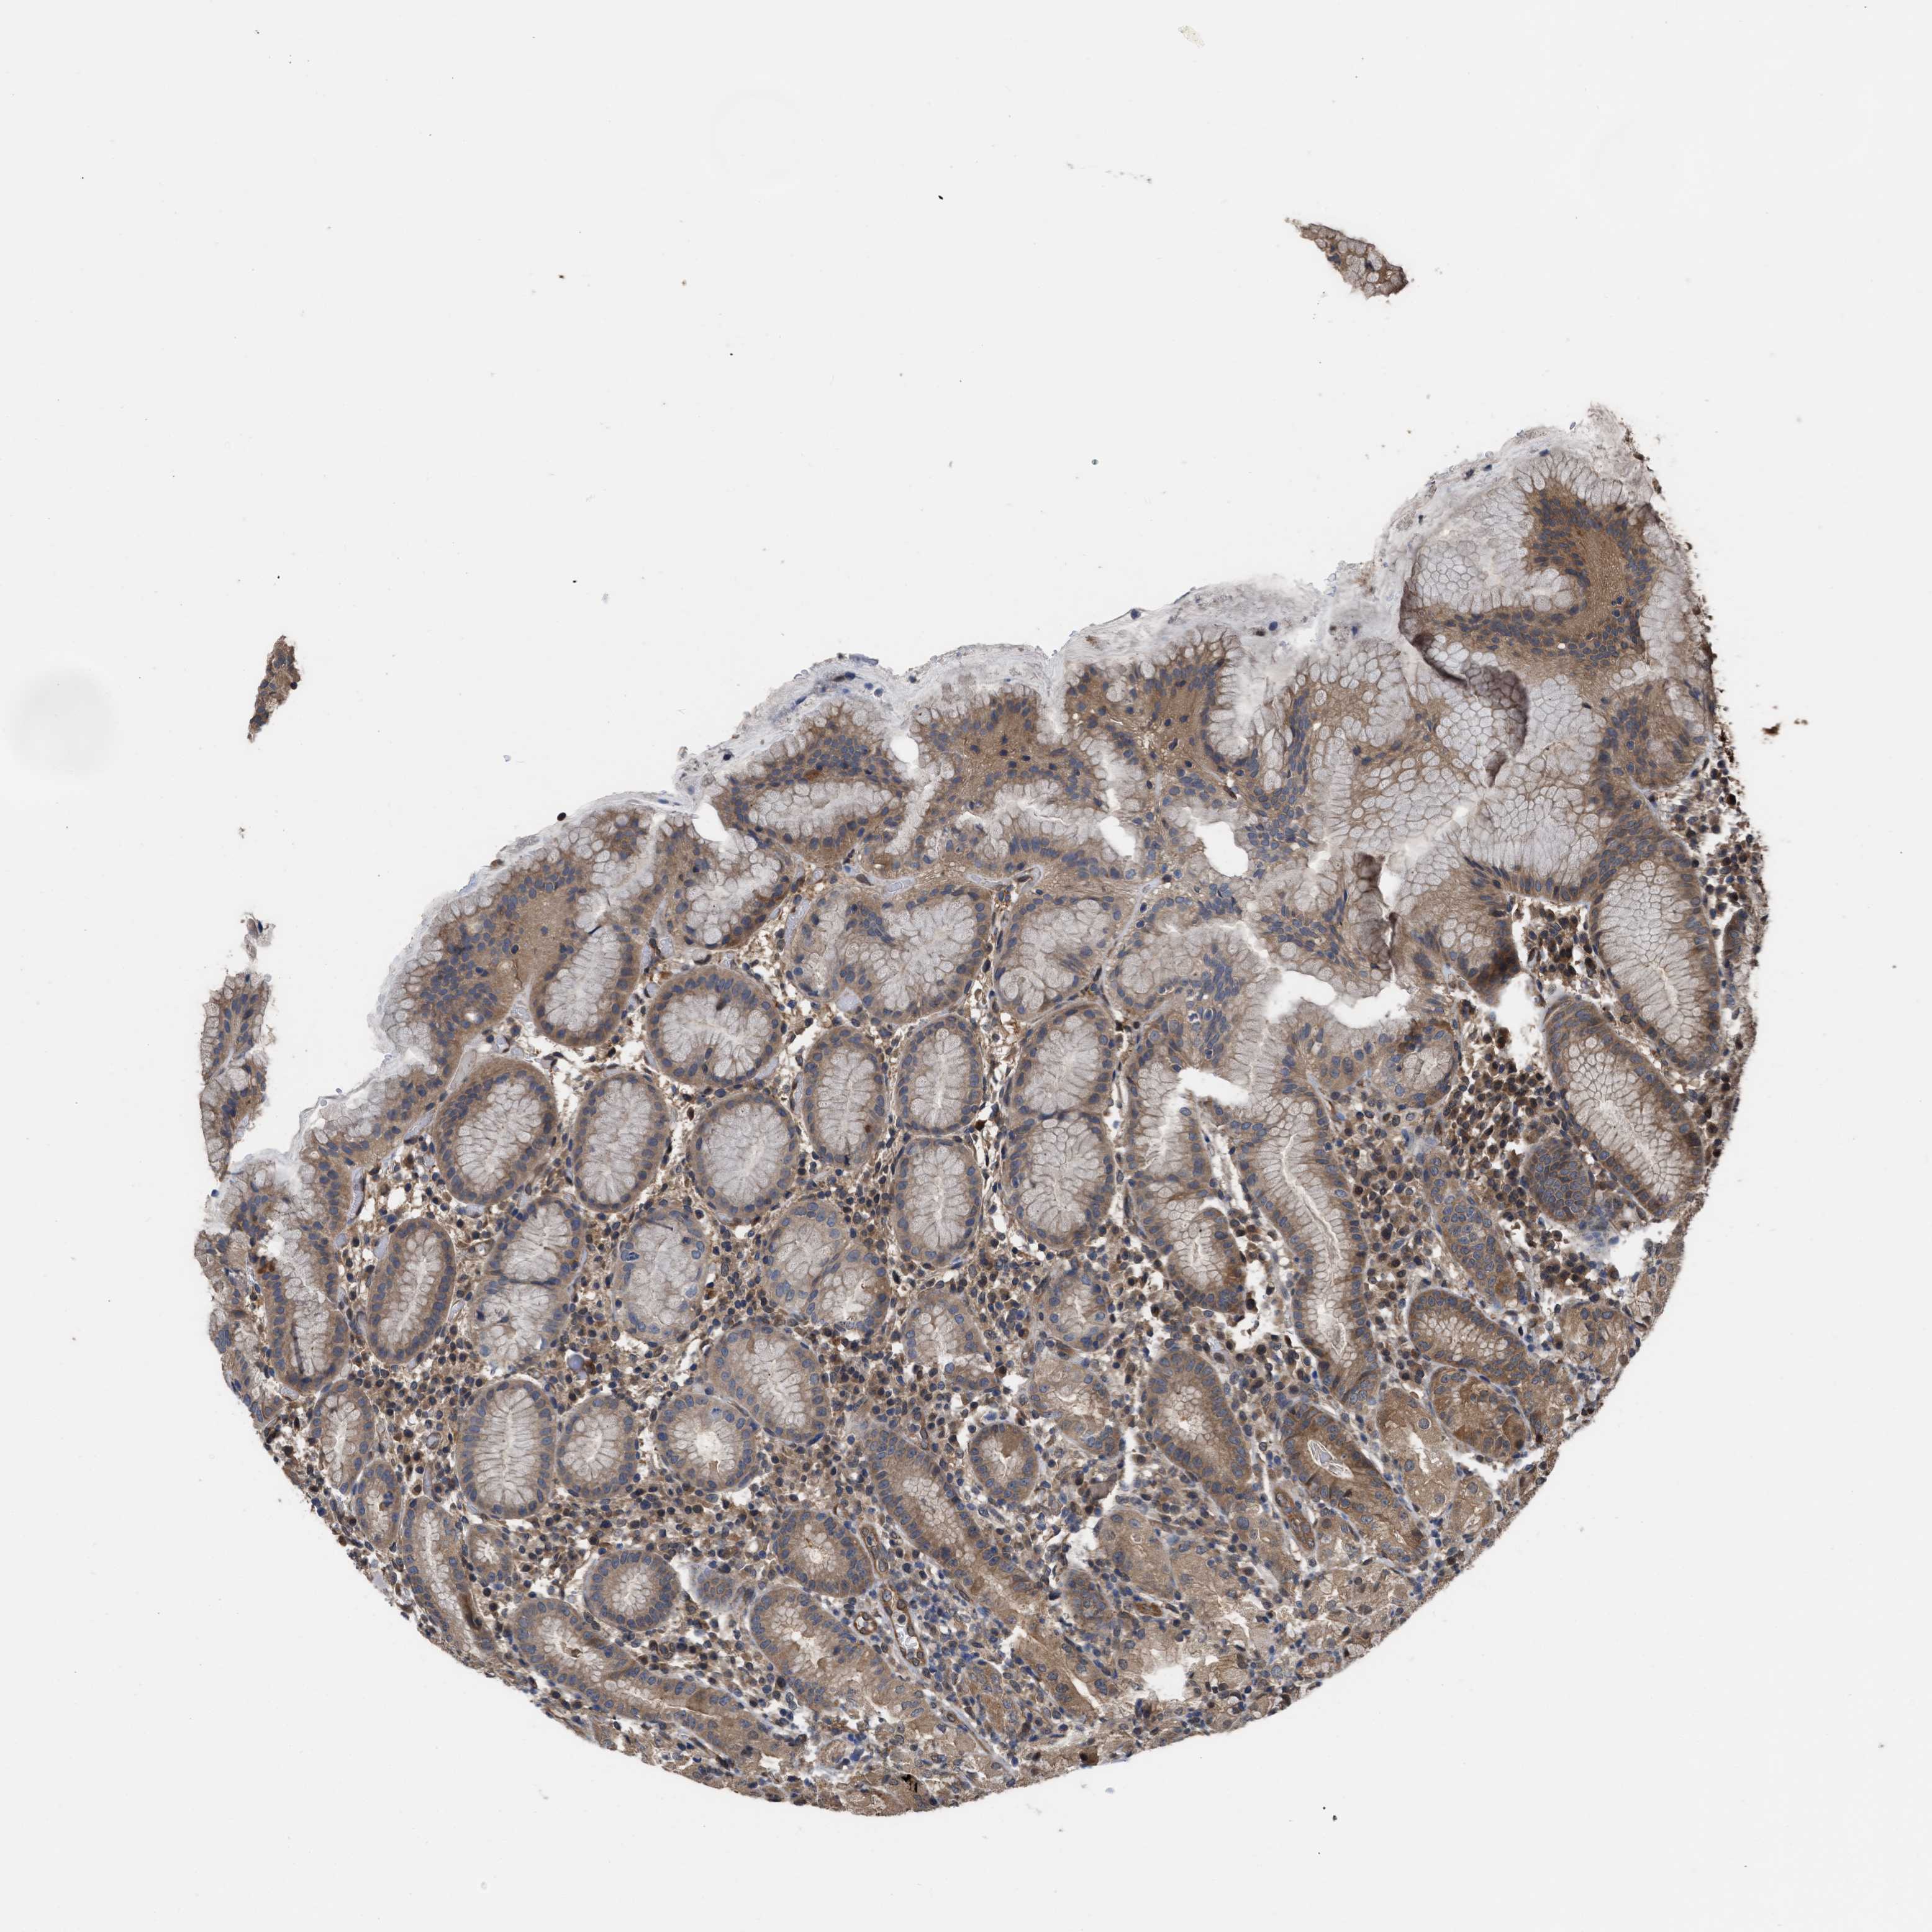

STOMACH 2 - Antibody stainingi

Antibody staining in the annotated cell types in the current human tissue is reported as not detected, low, medium, or high, based on conventional immunohistochemistry profiling in selected tissues. This score is based on the combination of the staining intensity and fraction of stained cells.

Each image is clickable and will lead to virtual microscopy that enables deeper exploration of all samples and also displays staining intensity scores, fraction scores and subcellular localization as well as patient and tissue information for each sample.

Antibody HPA026918Antibody CAB013274Antibody CAB018389

Glandular cells MediumHighMedium